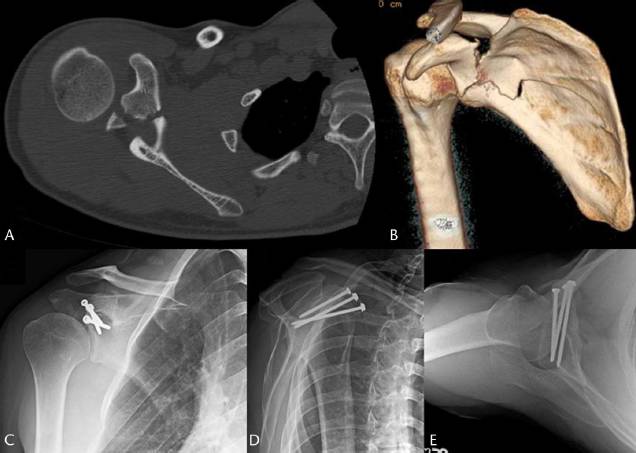

A-CT轴位影像学检查;B-3D CT重建后的影像学检查显示喙突骨折并移位,并且伴有肩胛骨的体部骨折;C-E:肩胛骨腋位片、轴位片显示使用3枚皮质骨螺钉固定后,骨折愈合良